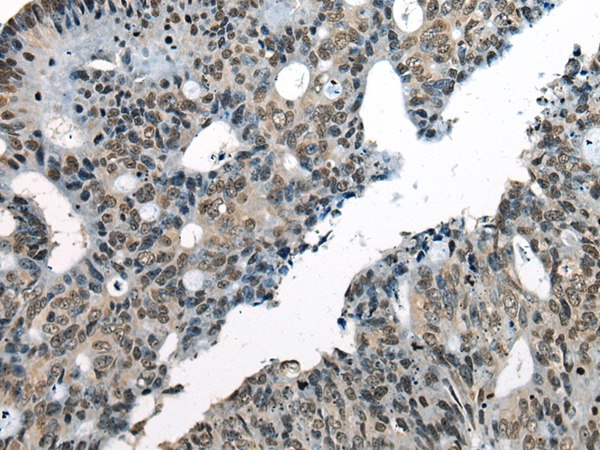

The image on the left is immunohistochemistry of paraffin-embedded Human colorectal cancer tissue using 46487(CHD1L Antibody) at dilution 1/30, on the right is treated with synthetic peptide. (Original magnification: x200)